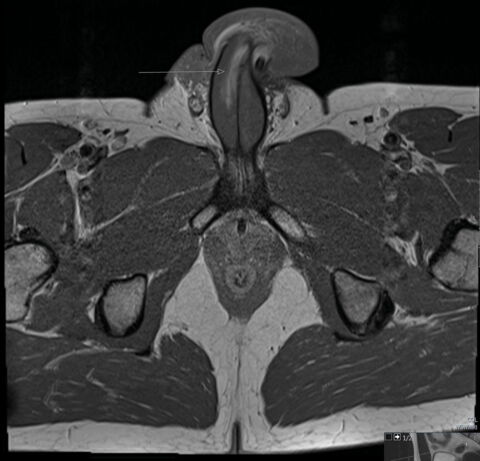

The BMJ explained that the unnamed victim’s penis ‘buckled against his partner’s perineum’ during a rather malaligned thrust, resulting in a 3cm vertical tear along the right side of the shaft. However, unlike typical penile breaks, our mystery Don Juan experienced only minor swelling and no audible popping. The man’s erection even managed to go down gradually, whereas most men unfortunate enough to break their joystick tend to go flaccid immediately.